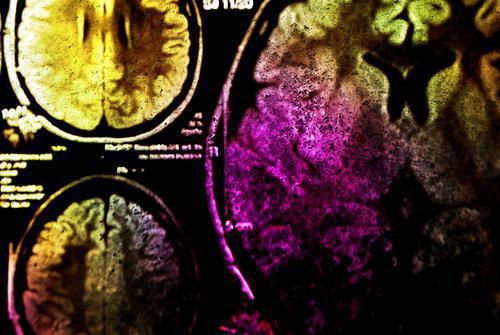

C’est en analysant l'ADN de plusieurs membres d'une même famille que les scientifiques ont découvert la mutation du gène ANGPTL6 chez les personnes qui présentaient un anévrisme cérébral. Des analyses ont ensuite été menées sur d’autres patients, démontrant des anomalies dans ce même gène. "Aujourd’hui, aucun test sanguin ne permet d’établir un diagnostic simple des anévrismes intracrâniens, le diagnostic ne pouvant se faire que par une IRM cérébrale, précisent les chercheurs. La mesure de l’activité de cette protéine, présente dans le sang, pourrait donc offrir la possibilité d’une détection simple et précoce des anévrismes intracrâniens et une évaluation du risque de rupture". En somme, cette découverte pourrait bien révolutionner le traitement des anévrismes cérébraux, prévenir les ruptures et anticiper les risques éventuels.